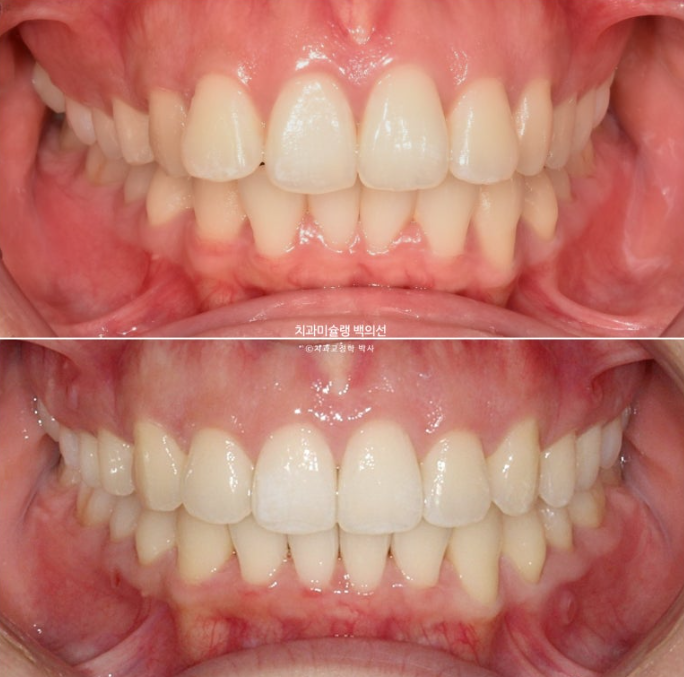

안모 비교 보겠습니다.

23.09~25.09

앞니 후방이동으로 비로소 입술이 편안하게 다물립니다.

스마일라인은 아랫입술과 평행하게 완벽한 호를 그립니다.

앞니가 뒤로 들어가면서 입을 다무는 것이 편해졌고